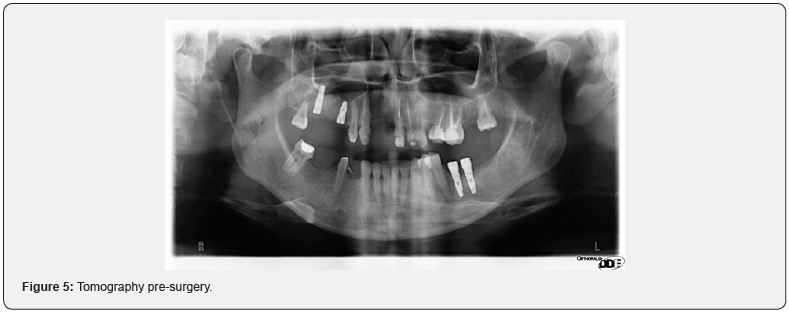

The implant insertion and the maintenance of the reduction of the lesion were evaluated on the panoramic examination following surgery.

The intrasinus graft appeared sufficiently integrated so as to allow a valid primary stability of the implant fixtures with an insertion torque greater than 30 Nm in both sites. A careful radiographic analysis of the right sinus cavity was therefore carried out, which underlined a clear radiolucency of the slaughtered sinus as evidence of the absence of recurrence of the lesion allowing a clear identification of the lower limits of the cavity. From a clinical point of view, the patient did not report any symptoms of sinus stasis, therefore the absence of pain corresponding to the maxillary sinus in question, the absence of nasal mucus and correct functionality of the corresponding ostium ad antrum. The persistence of an otolaryngological state of health meant that we proceeded four months later with the third surgical phase consisting in the uncovering of the implant fixtures and subsequently with the realization of the prosthetic products first provisional and after about 30 final days (Figure 5).